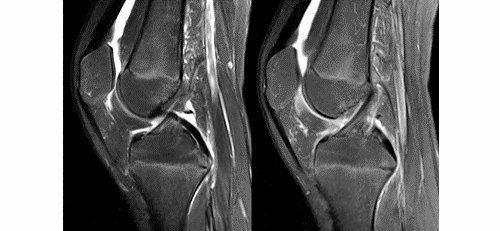

ACL的正常MRI表現——

1.各序列均為低信號。

2.韌帶平直,邊界清楚,有較好的張力。

3.韌帶內可有脂肪及滑膜條紋影。